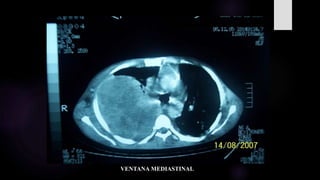

VENTANA PARENQUIMAL

VENTANA MEDIASTINAL